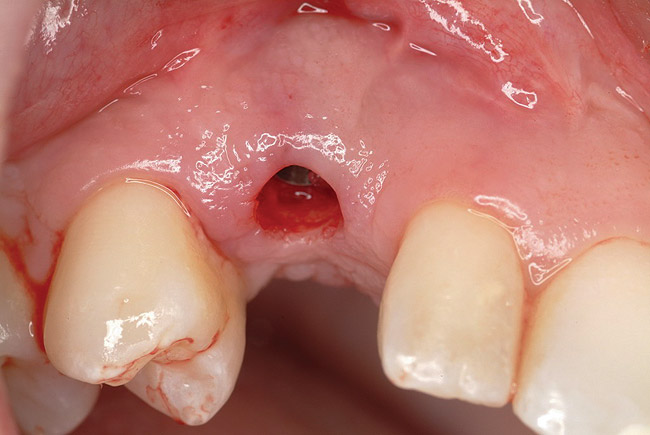

Figure 8  Primary stability of the implant achieved, facilitating a transmucosal healing approach.

Figure 8

Figure 9  Primary stability of the implant achieved, facilitating a transmucosal healing approach.

Figure 9

Approximately 4 months after grafting, the patient returned for clinical and 3-D radiographic evaluation. The thinnest area of ridge width preoperatively was remeasured in approximately the same location, demonstrating a gain of about 4 mm (Figure 7). The treatment plan was to place a 3.5-mm x 13-mm implant with a computer-generated guide (SiCat, Sirona Dental, www.sironausa.com), eliminating an additional open surgical procedure. Planning included initial osteotomy preparation with single-use drills combined with a localized ridge expansion using narrow, tapered osteotomes. This was performed approximately 5 months after the augmentation procedure, achieving primary stability of the implant, facilitating a transmucosal healing approach (Figure 8 and Figure 9). Following each step of osteotomy preparation, a probe was inserted along the walls of the site to confirm the integrity of the buccal and palatal walls prior to implant insertion.